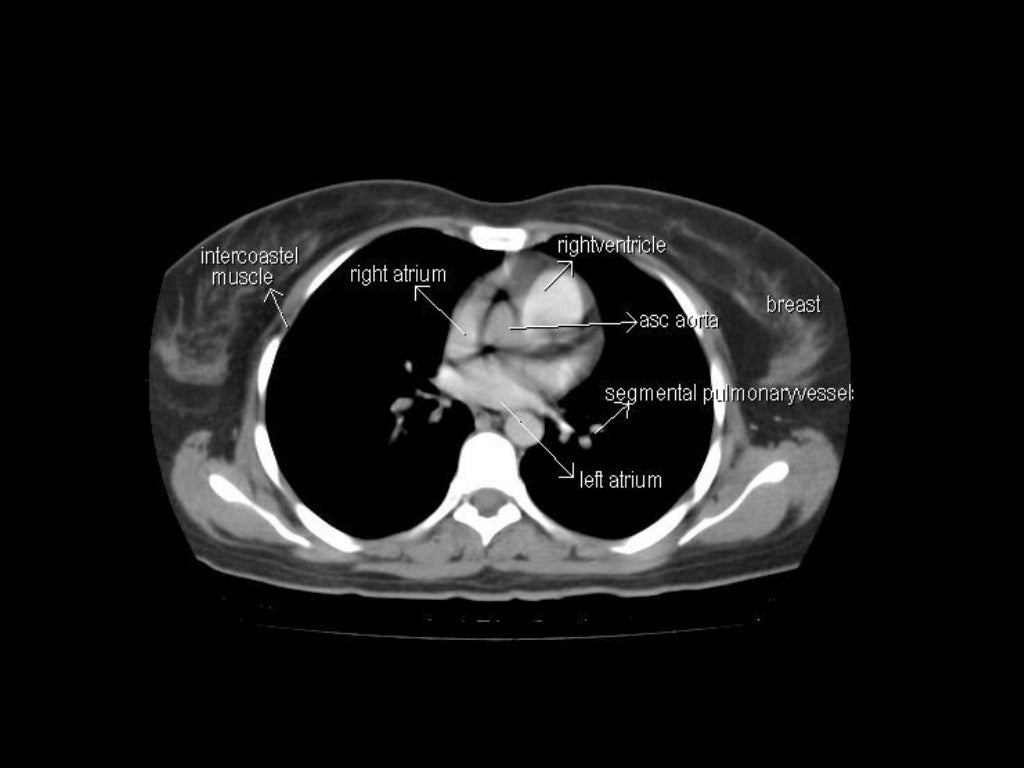

Chest Ct Anatomy Anatomical Charts & Posters Ct Anatomy Face This study is a normal ct of the face without intravenous contrast. Normal ct head with annotated and original images. This head and neck anatomy atlas is an educational tool for studying the normal anatomy of the face based on a contrast enhanced multidetector computed tomography imaging. Head first supine scan range: Annotated teaching ct head in standard and bone. Ct Anatomy Face.

CT Anatomy Ct Anatomy Face The acquisition parameters are as follows: Annotated teaching ct head in standard and bone windows. This study is a normal ct of the face without intravenous contrast. Anatomy labelled radiographs and ct/mri series teaching anatomy with a level of detail appropriate for medical students and junior residents. This head and neck anatomy atlas is an educational tool for studying the. Ct Anatomy Face.